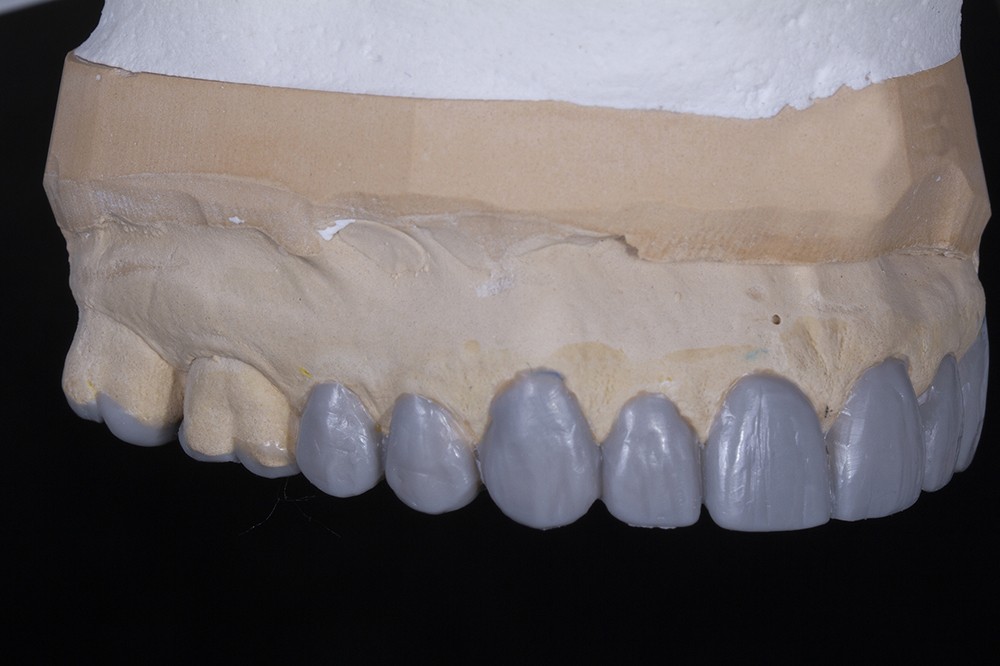

Dans un deuxième temps, un wax-up global permet de restaurer les courbes d’occlusion. Il est à noter que la présence d’égressions dentaires, faute d’antagoniste ou d’anciennes restaurations prothétiques inadaptées, crée des usures inégales au sein de la cavité buccale. Aussi, la présence de zones non recouvertes par le wax-up dans les secteurs postérieurs est courante, permettant ainsi la préservation de zones amélaires majeures pour le collage (fig. 2).

Le wax-up est le point de départ pour la réalisation de temporisations en technique d’isomoulage. Pour cela, le repositionnement de la clé en silicone s’effectue grâce à la réalisation de butées d’enfoncement sur des zones non waxées ou volontairement déwaxées (fig. 3).